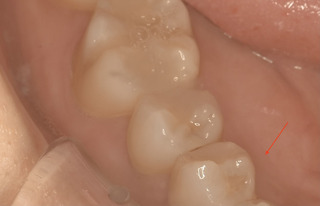

上から削っているところ なかなか根管口が見つからないので、レントゲンで位置を確認。

もうちょいだ。

方向は間違えていないので、追随。

ガッタパーチャ(前医が入れた根の中に入っているお薬)が見えてきました。

(まだ先の難関はあるが、ここまでくるとちょっとホッとします)